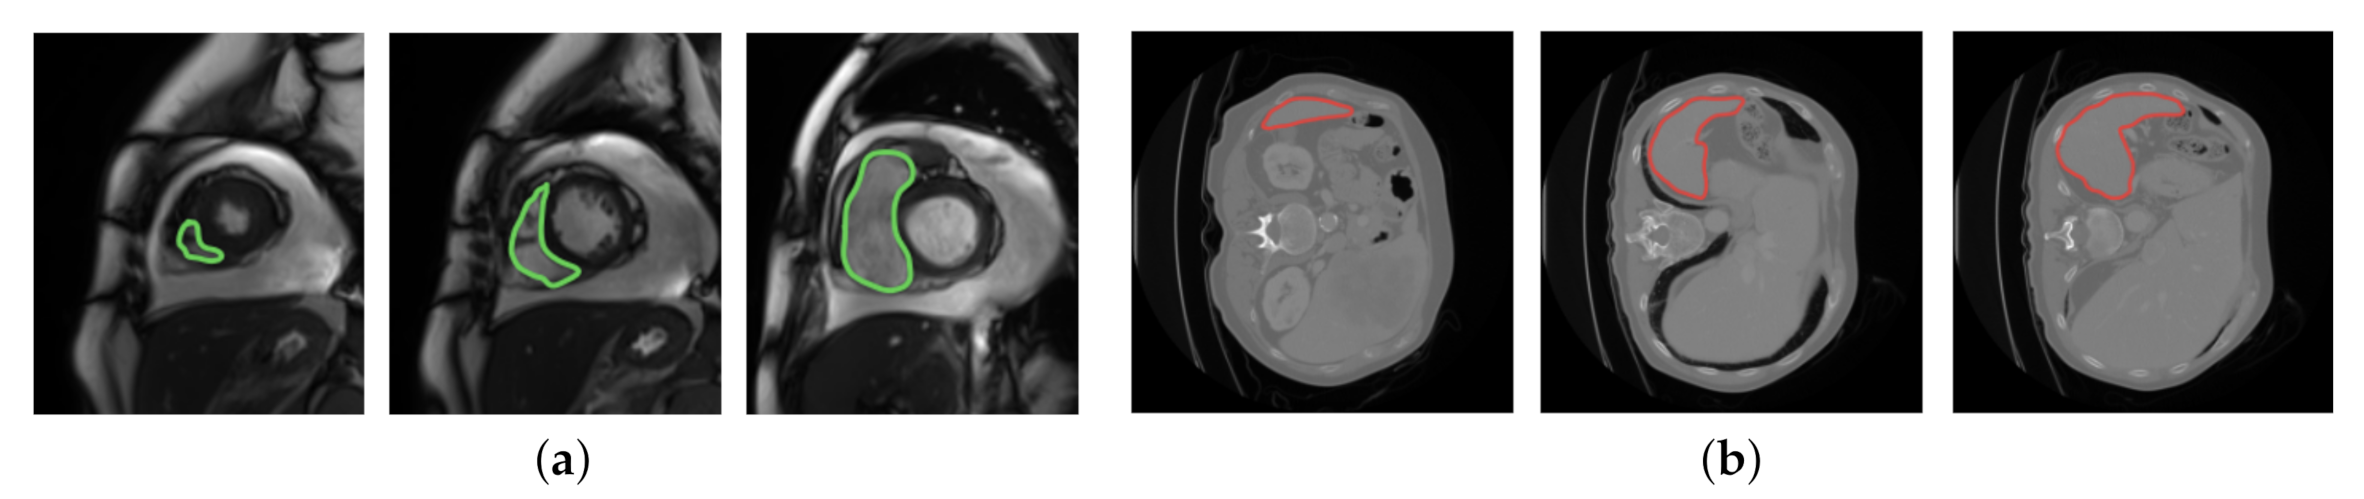

Even though MAML and Reptile use prior knowledge to choose parameters that generalize well from few examples, both algorithms limit the diversity of the task distribution that they can learn from in medical image segmentation. Specifically, MAML updates the initial parameter vector towards the direction of a query-testing phase, which limits the capability of updating the initial parameter vector by learning from the tasks in the support-training phase. Reptile limits the ability of updating the model parameters since it does not learn from diverse tasks in the inner loop. In order to counter the limitations in MAML and Reptile, we propose to augment both algorithms with the capability to learn from diverse segmentation tasks across the entire task distribution. Specifically, our algorithm aims to learn from the diversity of image features which characterize a specific tissue type while showing diverse signal intensities. The reason that the proposed idea can benefit from signal intensities is described as follows. In MRI, the terms low, intermediate, and high signal intensities are used. Depending on the scan protocol, a tissue type is imaged as white if it has high signal intensities, as gray if it has intermediate signal intensities, and as dark gray/black if it has low signal intensities. We focus on a class of tissue types which move often: the heart is moving as it beats, the colon is moving as it digests, etc. Due to the movement, these tissue types show diverse image features regarding location, size, shape, and impact on the surrounding area. The image features are described by diverse signal intensities, such as high, intermediate, and low. The learning capability is therefore enhanced if we can learn from the diversity of image features which characterize a specific tissue type while showing diverse signal intensities. Figure 1 displays two example tissue types; each one shows diverse image features regarding location, size, shape, and impact on the surrounding area.

Figure 1.

The diversity of image features in two example tissue types: heart (left) and spleen (right). The image features are segmented by green and red lines in the heart and spleen, respectively. (a) Heart; (b) spleen.